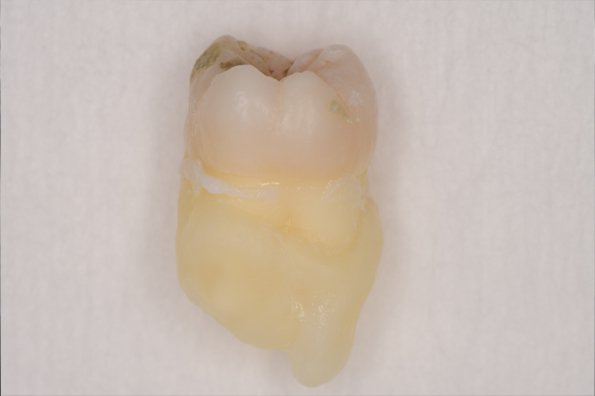

CASE 2

| 年齢・性別 | 30代・男性 |

|---|---|

| 主訴 | 左上下親知らず抜きたい |

| 抜歯期間 | 30分 |

| 抜歯費用 | 約2,500円(保険内) 別途CT撮影で3,000円 |

| 抜歯内容 | 左上下の親知らず抜歯 |